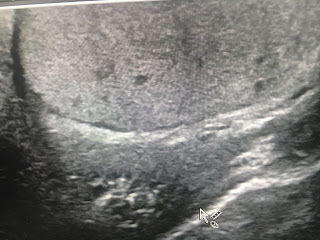

There was a hard firm swelling in the right testis and an Ultrasound of the testis showed diffuse hypoechoic mass suggestive of a neoplastic lesion.